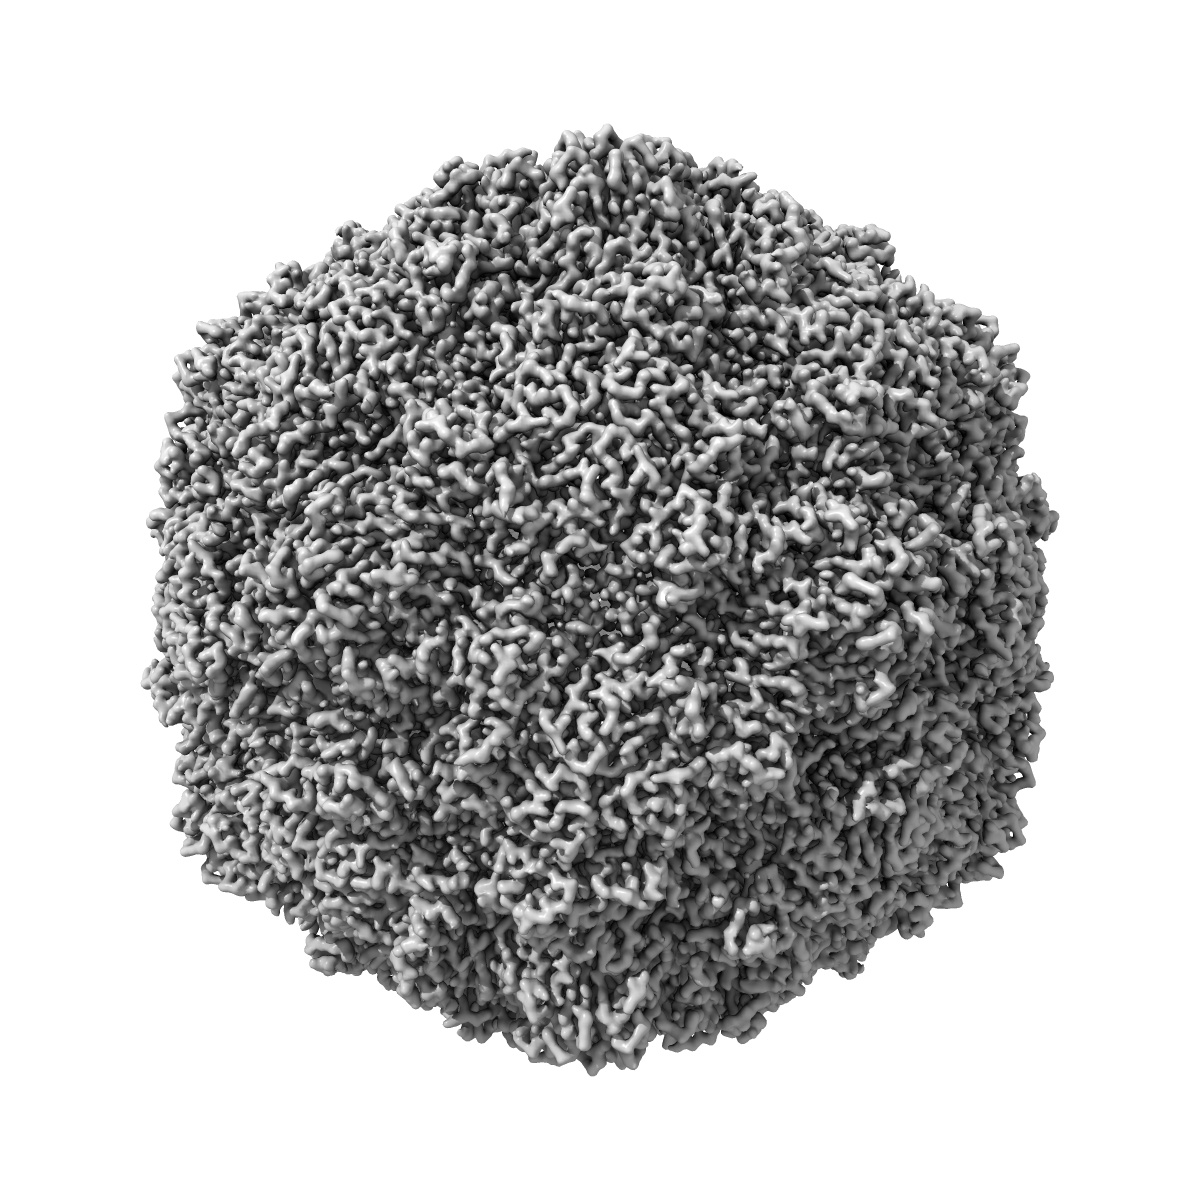

Coxsackievirus A9 bound with compound 14 (CL275)

Single-particle2.31 Å

SAR Analysis of Novel Coxsackie virus A9 Capsid Binders.

(2024) J Med Chem , 67 , 17144 - 17161